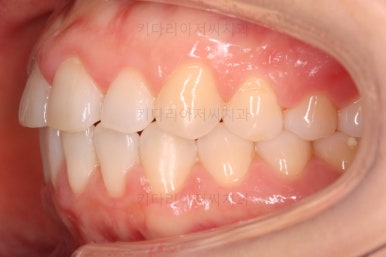

부산나비앞니교정 키다리아저씨치과에 처음 내원하셨을 당시의 입 안 모습입ㄴ디ㅏ.

보시다시피 위아래 정중앙에 있는 치아가 V자 형태로 꺾여있었어요.

흔히 "나비치아", "나비앞니"라고 표현을 하는데 나비 날개짓을 하듯이 꺾여 있다고 그렇게 부릅니다.

어금니쪽의 맞물림은 굉장히 양호한 편이였기 때문에 부분교정에 딱 알맞는 경우였어요.